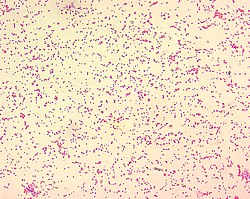

Brucella spp. are gram-negative in their staining morphology. Brucella spp. are poorly staining, small gram-negative coccobacilli (0.5-0.7 x 0.6-1.5 µm), and are seen mostly as single cells and appearing like "fine sand".

Brucella abortus is a Gram-negative bacterium in the family Brucellaceae and is one of the causative agents of brucellosis. The rod-shaped pathogen is classified under the domain Bacteria.[1] The prokaryotic B. abortus is non-spore-forming, non-motile and aerobic.[2]